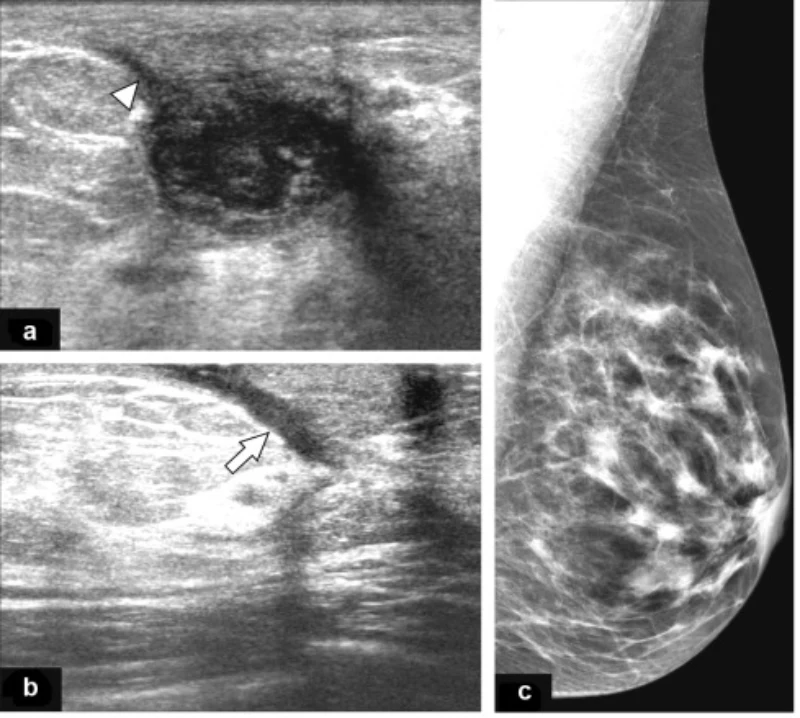

اهمیت انجام سونوگرافی در ماستیت پستان

سونوگرافی پستان یکی از مهمترین ابزارهای تشخیصی در بررسی ماستیت است. این روش تصویربرداری بدون درد و بدون اشعه بوده و به پزشک کمک میکند تا وضعیت بافت پستان را بهدقت ارزیابی کند.

با کمک سونوگرافی میتوان بین التهاب ساده، تجمع شیر، آبسه پستان و سایر تودههای پستانی تمایز قائل شد. در مواردی که توده دردناک یا تورم غیرطبیعی وجود دارد و با درمان اولیه بهبود پیدا نمیکند، انجام سونوگرافی ضروری است.

همچنین در زنان غیرشیرده یا در ماستیتهای عودکننده، سونوگرافی نقش مهمی در رد بیماریهای جدیتر مانند تودههای مشکوک یا سرطان التهابی پستان دارد. بنابراین، انجام سونوگرافی بهموقع میتواند از تشخیص اشتباه و تأخیر در درمان جلوگیری کند.

چه زمانی انجام سونوگرافی پستان ضروری است؟

اگر توده دردناک پستان با درمان اولیه بهبود نیابد، تب ادامهدار باشد، یا احتمال آبسه وجود داشته باشد، انجام سونوگرافی پستان ضروری است. همچنین در زنان غیرشیرده یا ماستیتهای عودکننده، سونوگرافی برای بررسی دقیقتر توصیه میشود.

تفاوت ماستیت با آبسه پستان چیست؟

ماستیت به التهاب و گاهی عفونت بافت پستان گفته میشود، اما آبسه پستان مرحله پیشرفتهتری است که در آن چرک در یک ناحیه تجمع پیدا میکند. آبسه معمولاً نیاز به تخلیه و درمان تخصصی دارد و با سونوگرافی تشخیص داده میشود.